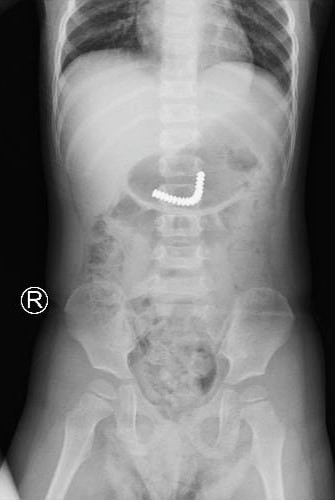

Hình ảnh nội soi thấy các viên bi nam châm dính chùm trong bụng bệnh nhi (ảnh: BVCC) Qua chụp phim kiểm tra, các bác sĩ thấy dị vật trong dạ dày nên nhanh chóng đưa bệnh nhi đưa đi nội soi tiêu hoá khẩn. Tại đây, bác sĩ thấy dị vật đã xuống ruột non nên kíp trực quyết định khẩn trương mổ nội soi thám sát.

BS CK1 Đỗ Huy Trọng Hiếu nhẹ nhàng đưa đoạn ruột phình chứa dị vật ra vết mổ chỗ rốn, mở hỗng tràng lấy dị vật (18 viên nam châm) dính kết chùm lại. Sau mổ, bệnh nhi đang hồi phục tốt và dự kiến xuất viện sau vài ngày tới.